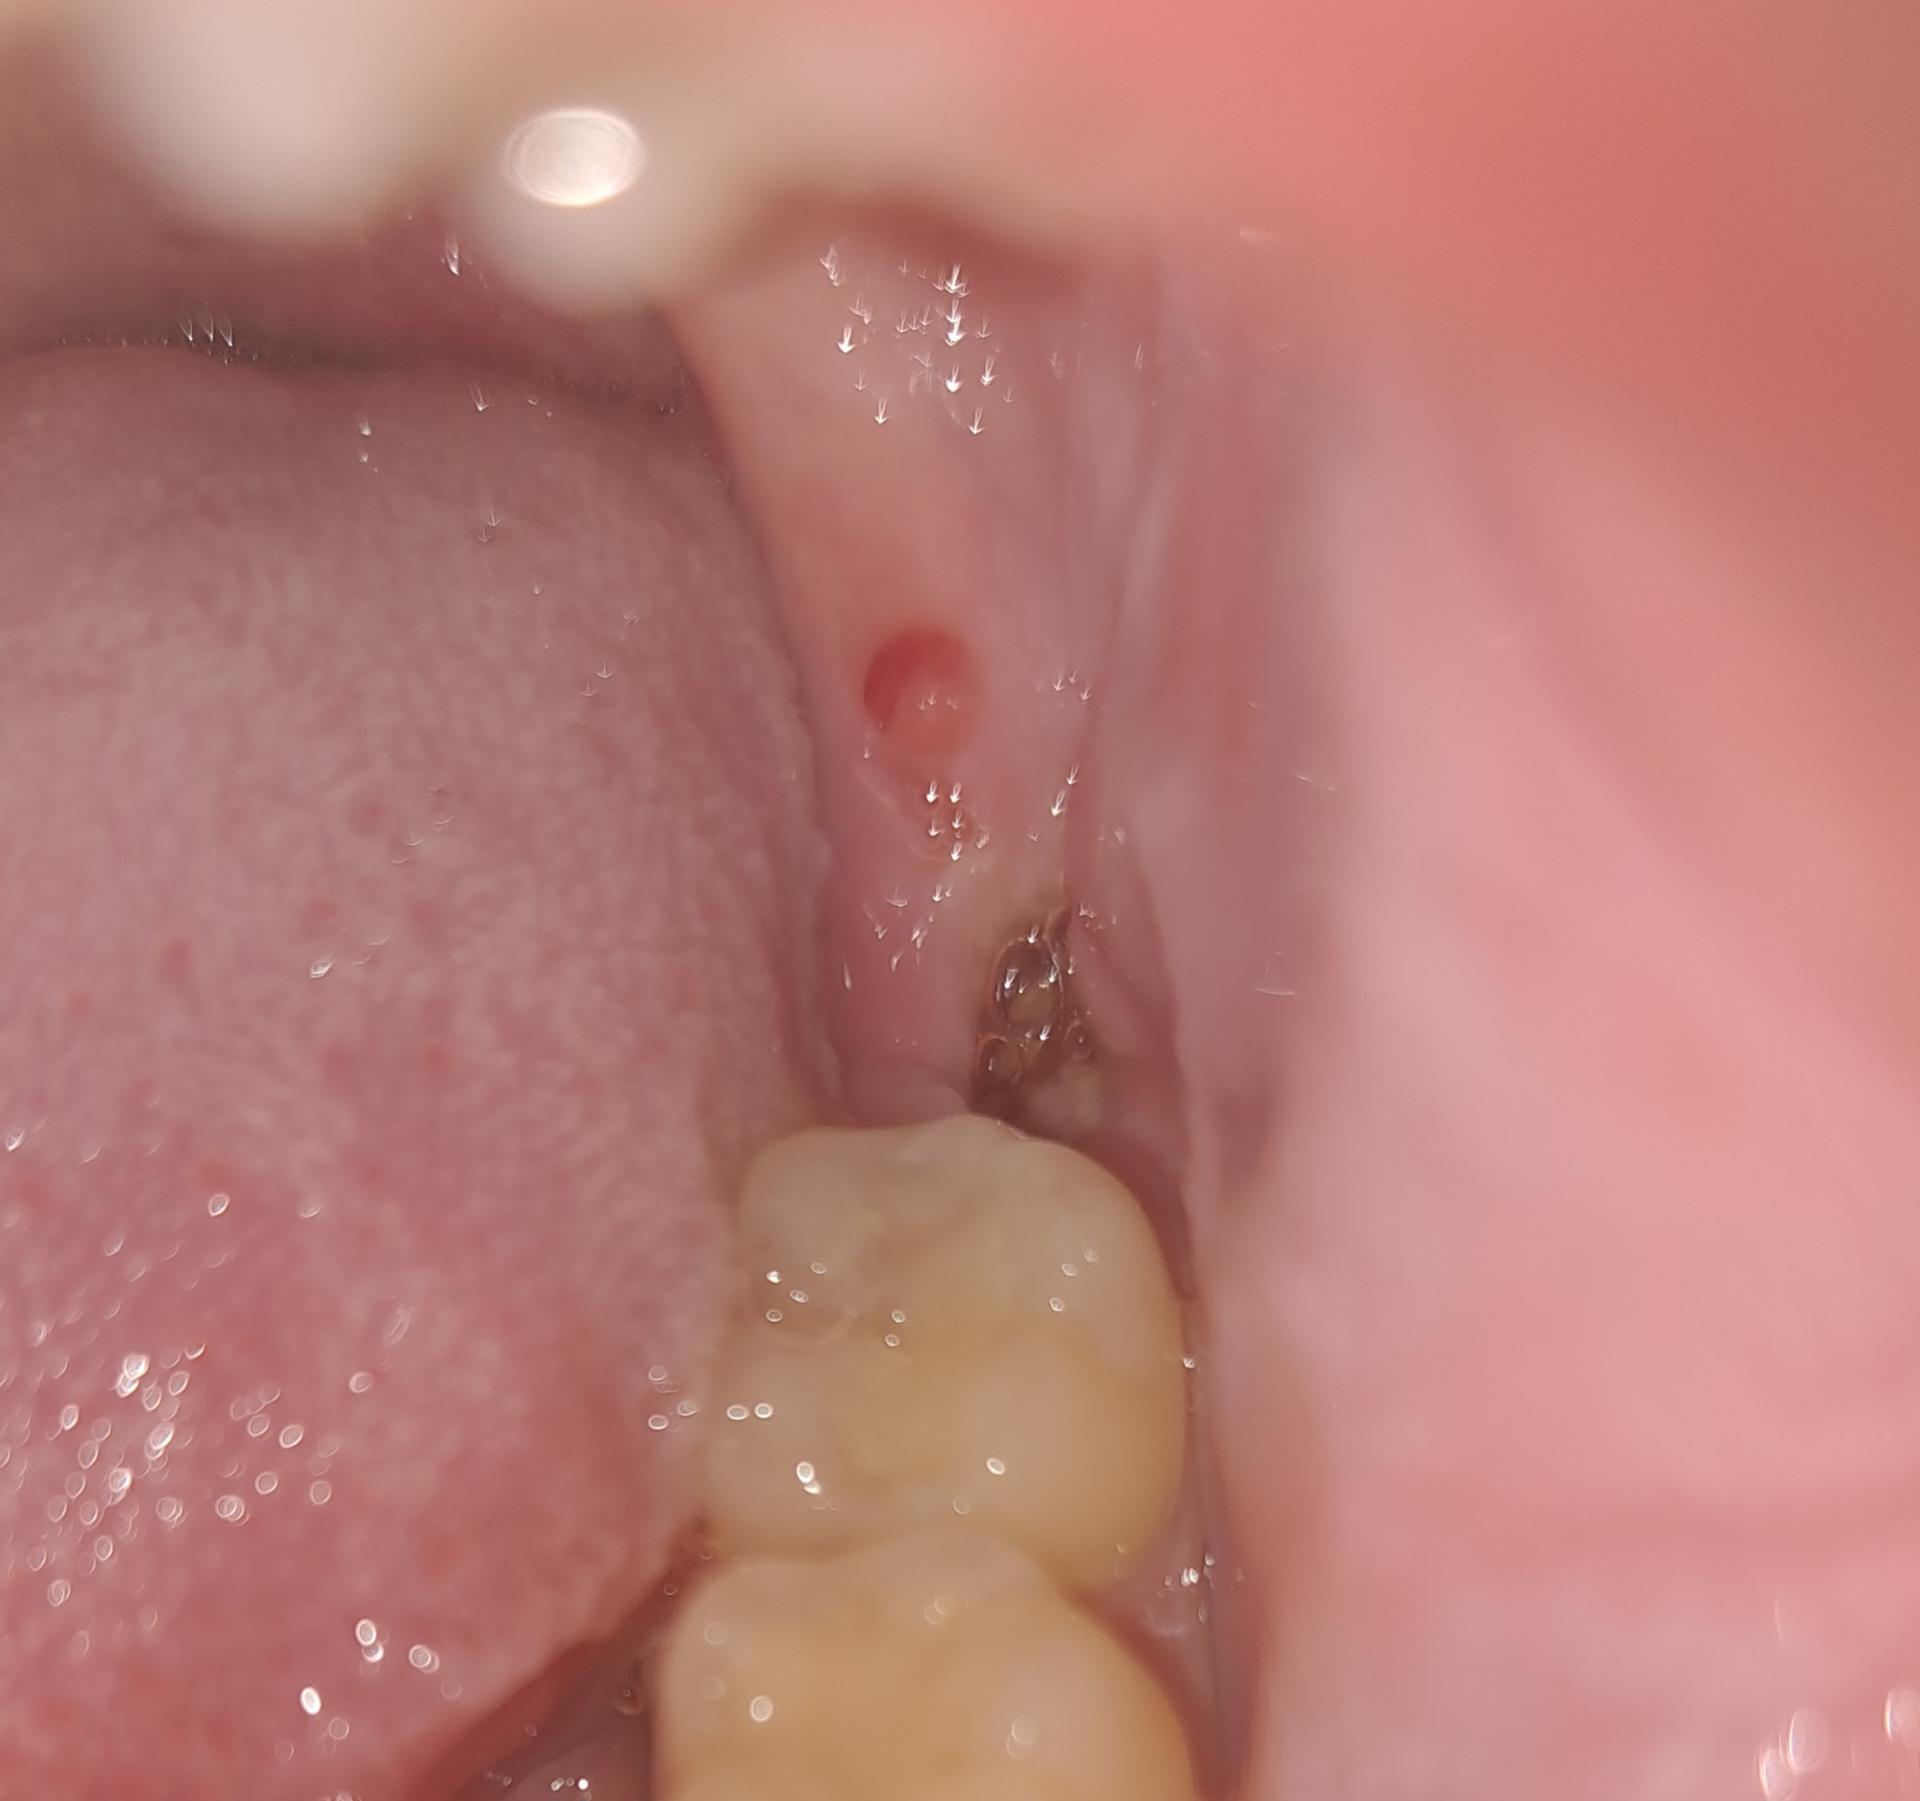

사랑니 발치 4일차, 실밥 제거 후 갑작스러운 통증

안녕하세요 4일 전에 왼쪽 아래 사랑니 발치했습니다.

사랑니 발치 4일차에, 치과의사선생님의 진단으로 실밥을 제거했습니다.

실밥 제거 당일인 오늘, 자다가 갑작스럽게 뚝 끊어지는 듯한 통증으로 깼습니다. 혈전이 없고 잇몸 일부분이 따끔거립니다. 피맛이 조금씩 계속 나고 있고, 발치 부위가 부은 듯한 느낌도 있고요... 턱과 귀가 얼얼합니다.

보통 실밥제거를 한 이후에도 드라이소켓일 수 있는 걸까요..? ㅠㅠ

• 1번 째 사진

사진상 치유에 별다른 문제는 없어보입니다 혈전은 원래 발치 후 48시간 내 흡수되어 안보이는게 맞습니다 통증이 있다면 상비약 진통제 드셔도 됩니다

실밥을 제거하기 전까지 특별히 문제가 없었다면 그 후에 드라이소켓의 가능성은 거의 없습니다.